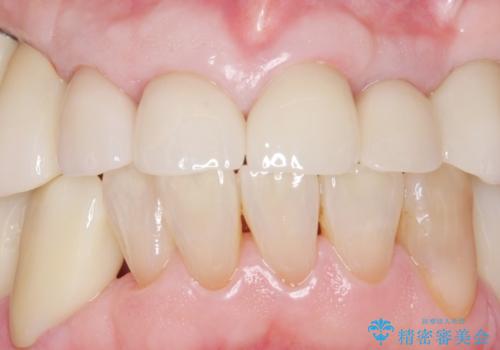

審美的な仕上がりと自然な咬み心地に喜んで頂けました。

治療前は口元を隠すようにお話しされていたのですが、治療後はそれもなくなり、満面の笑顔を見せて下さいました。

クラウンの種類:オールセラミッククラウン スタンダード